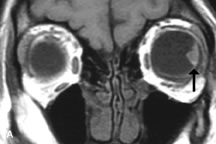

Pleomorphic adenomas demonstrate long T1 and T2 signal characteristics. They may show heterogeneity on T2-weighted images74 and moderate to marked enhancement with contrast.75 Signal characteristics of adenoid cystic carcinoma include hypointensity to fat on T1-weighted images, hyperintensity to fat with increased T2 weighting, and isointensity to fat on proton density-weighted studies (Fig. 23).31,75 Secondary bony alterations of the lacrimal fossa associated with lacrimal gland tumors, such as remodeling (benign mixed tumor) or destruction (adenoid cystic carcinoma), are seen indirectly on MR images; however, bone windows on CT scans provide better delineation of these changes. In contrast to the round or globular appearance of benign or malignant epithelial tumors of the lacrimal gland, lymphoproliferative tumors usually appear to be molding or draping onto the globe and the surrounding bony orbit.

Fig. 23. A. T2-weighted and (B and C) postcontrast fat-suppressed T1-weighted MR scans demonstrate an infiltrative lacrimal region mass than invades the lateral rectus muscle (arrows). This highly cellular lesion is seen to have a very hypointense appearance on the T2-weighted scan.